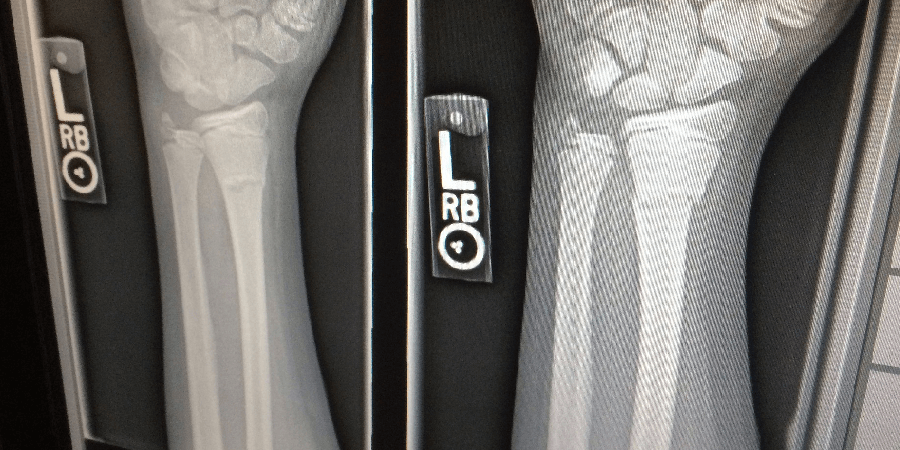

Da esquerda para a direita: osso normal, osteopenia, osteoporose e osteoporose severa.

O teste é indolor e rápido. Calcula quão densos ou grossos são seus ossos usando raios-X.